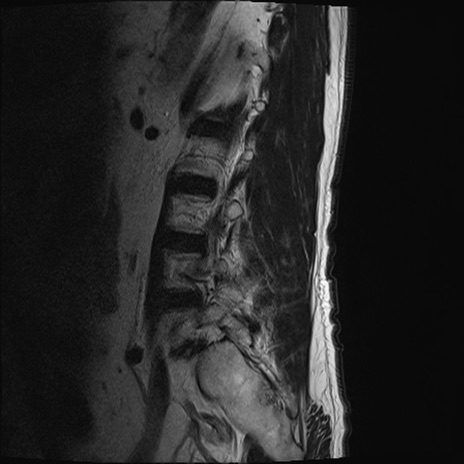

【整形】TIPS症例2 腰椎MRI T2WI(矢状断像)

【症例】70歳代男性

【主訴】左下肢痛

【現病歴】2週間前くらいから腰痛、左下肢痛あり。左臀部から大腿、下腿外側のしびれが常時ある。歩行とともに同部位の痛みあり。

【身体所見】Lasegue70-/60+、Bragard-/±、PTR ±/±、ATR -/-、IP 5/5、TA 5/4、TS 5/5、EHL 右第1足趾なし/3、FHL 5/5、hypersthesia(-)、足背動脈触知良好

異常所見と診断は?